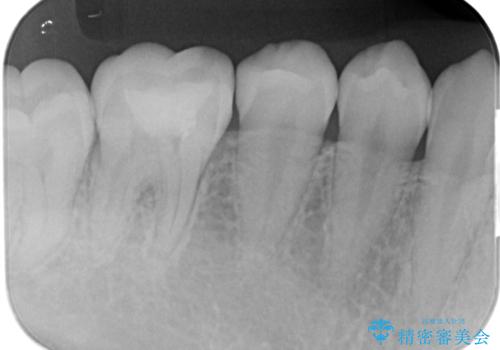

拡大鏡下で古い樹脂を除去し、虫歯がない事を確認してe-maxインレーで治療を行いました。

適合の良い詰め物が入りました。

セラミックは虫歯の再発のリスクが少ないです。